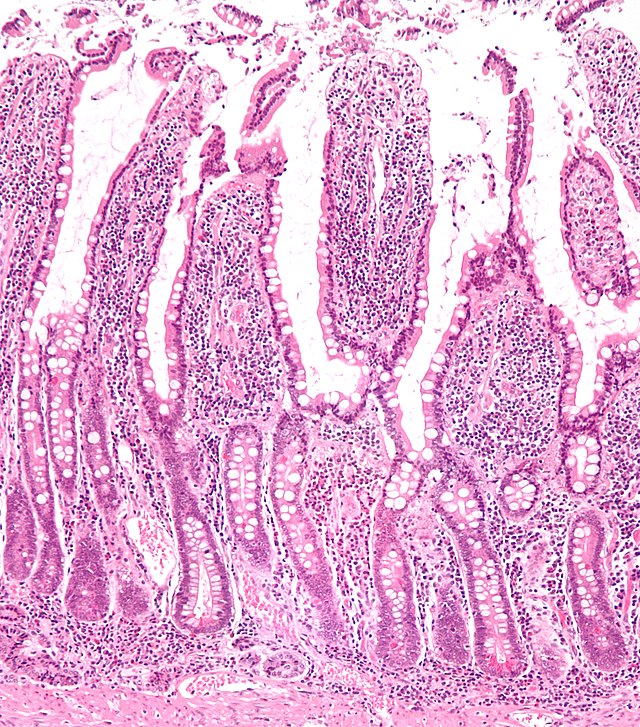

Villi och mikrovilli (tarmludd) i tunntarmen. - Villi & mikrovilli

- Mikrovilli gör att tarmens yta blir mycket stor – 30 m2 (referens)!

- Blodkärl & lymfkärl

- Näringsämnena absorberas